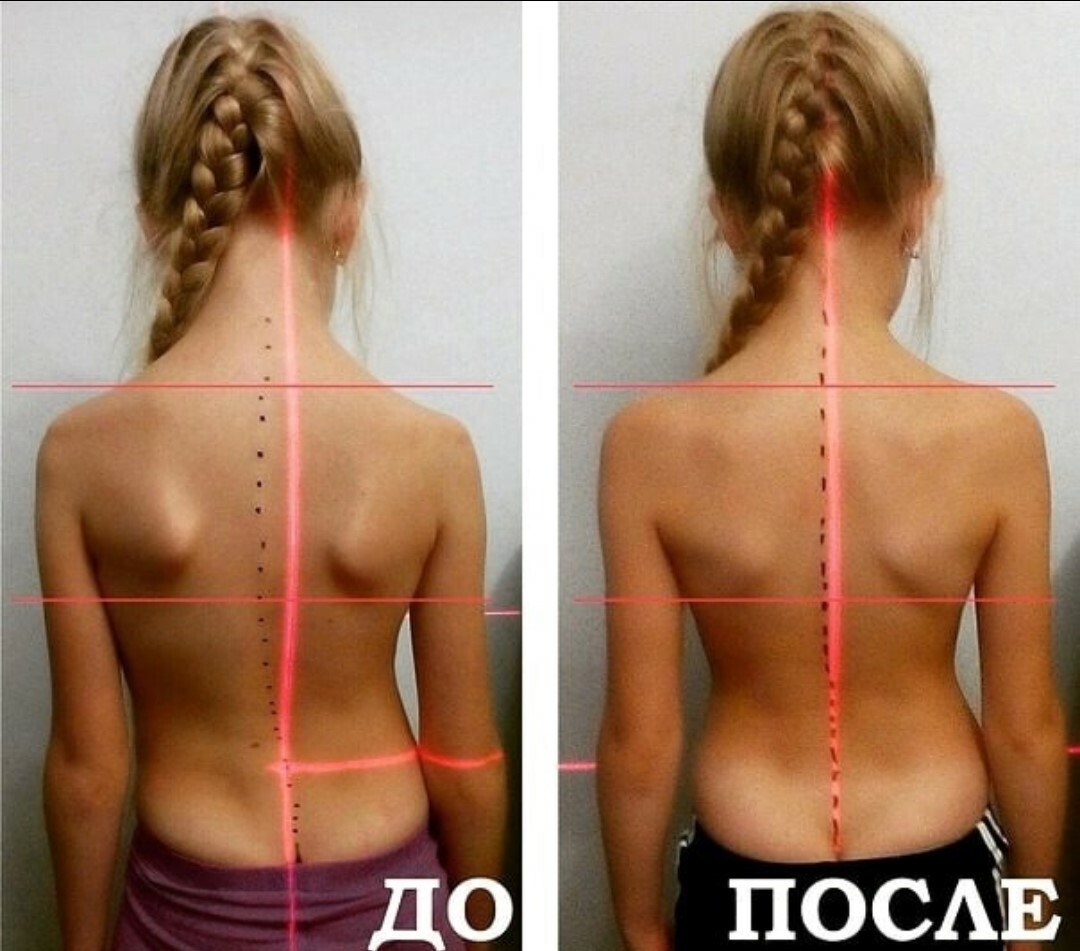

Искривление позвоночника: причины и последствия на снимках

Раздел: Визуальный дайджест